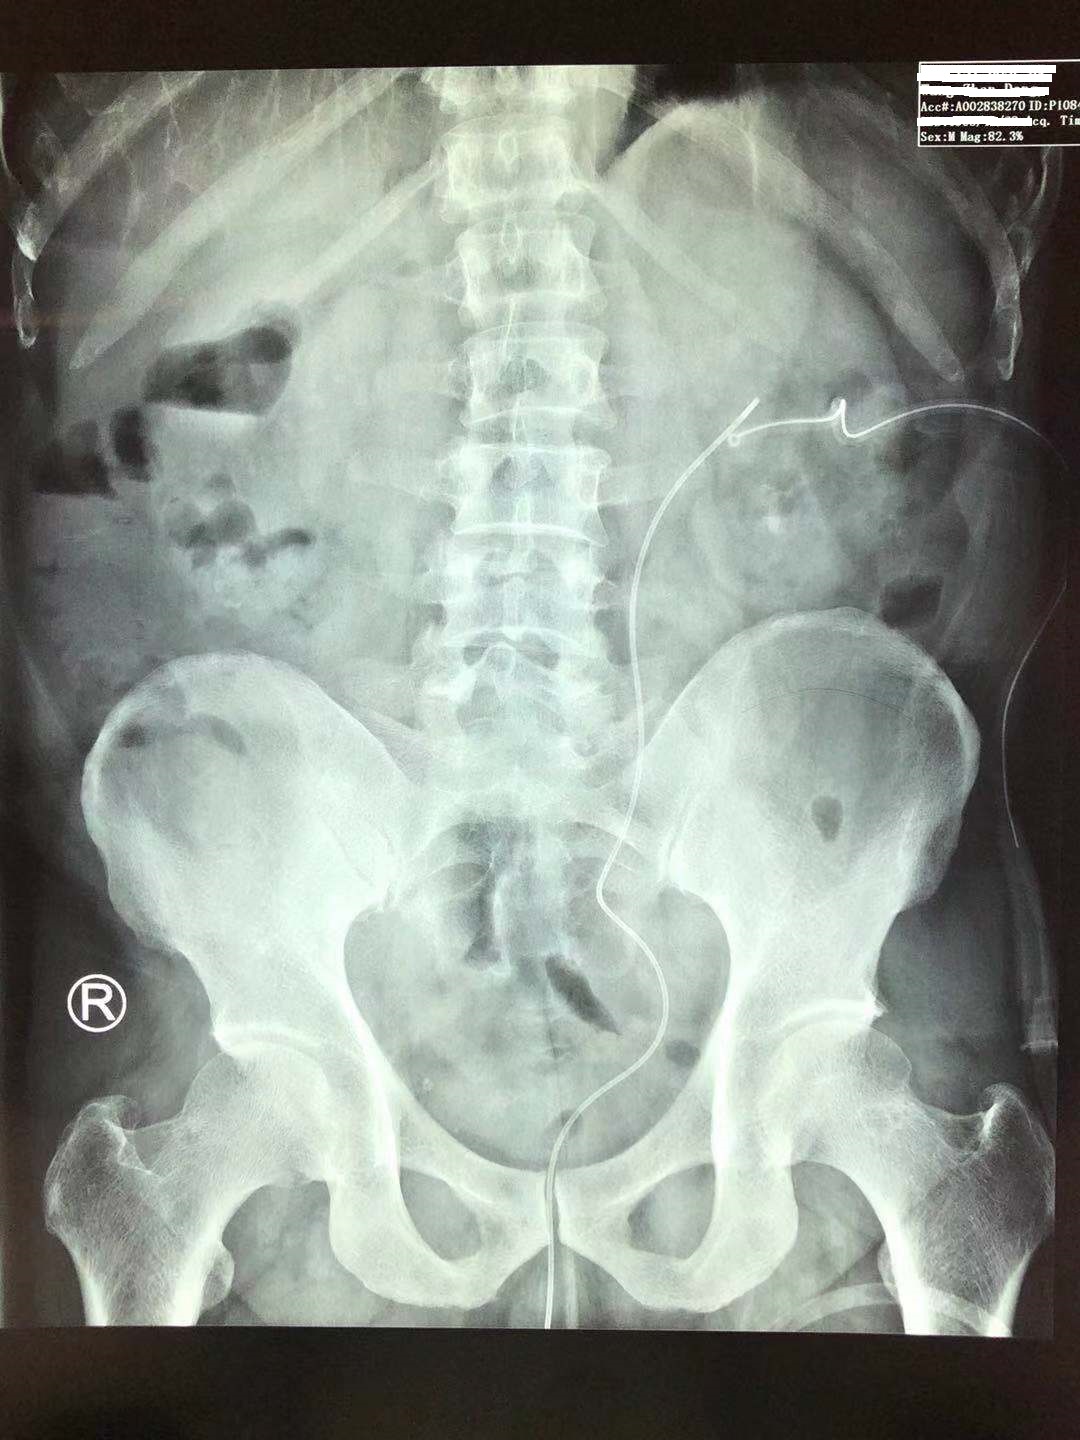

37岁的林先生是一名来自湖南的美团送餐员,由于"反复腰痛不适、下肢浮肿半年"来到我的门诊看病。经过泌尿系CT和腹部X线检查后,发现林先生的双侧肾脏集合系统长满了结石(双侧鹿角形结石),更要命的是,他的肾功能也处于尿毒症期的边缘。

林先生的双肾鹿角形结石